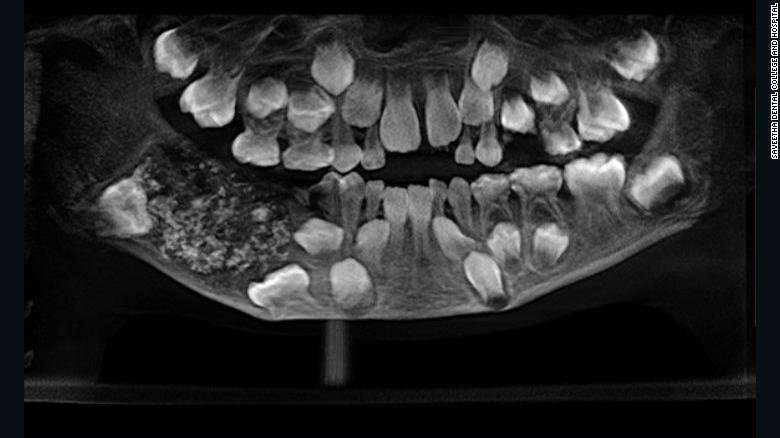

Tháng trước, cậu nhóc sống ở phía nam thành phố Chennai được bố mẹ đưa đến bệnh viện trong tình trạng hàm dưới bên phải đau và sưng húp. Sau khi chụp X quang, bác sĩ Prathiba Ramani - Trưởng khoa Răng hàm mặt tại Bệnh viện Nha khoa Saveetha - bàng hoàng phát hiện khoang miệng của cậu hình thành nên một nang chứa đầy răng với số lượng lên đến 526 chiếc!

Túi nang chứa đến hàng trăm chiếc răng nhỏ vụn khiến cậu bé đau đớn.

Dù cuộc phẫu thuật loại bỏ “chiếc túi” kỳ dị đã diễn ra từ tháng trước, các bác sĩ vẫn phải lần lượt thăm khám và kiểm tra từng chiếc răng một để xác thực chẩn đoán của họ. Hai nha sĩ đã tách chiếc “túi răng” khỏi miệng cậu bé, sau đó, họ mất thêm 5 tiếng đồng hồ để hoàn toàn loại bỏ số răng mọc không đúng chỗ.

Kích thước của các mẩu răng dao động từ 0,1 - 15 mm.

Ba ngày sau cuộc phẫu thuật, cậu nhóc đã được xuất viện. Bác sĩ Ramani cho biết: “Có tổng cộng 526 chiếc răng được loại bỏ khỏi miệng cậu bé, mỗi chiếc có kích thước từ 0,1 đến 15 mm. Ngay cả mẩu nhỏ nhất cũng đã hình thành thân, chân và lớp men như một chiếc răng bình thường. May mắn là hiện giờ tình trạng của bé đã ổn định, có thể hồi phục và phát triển khỏe mạnh trong thời gian tới”.

Ramani nhận định cậu bé đã mắc phải bệnh lý hiếm gặp mang tên u răng đa hợp kép. Nguyên nhân dẫn đến tình trạng này còn chưa được làm rõ, nhưng cô cho rằng đây có thể là vấn đề về di truyền hoặc hậu quả của các tác động bên ngoài như phóng xạ.